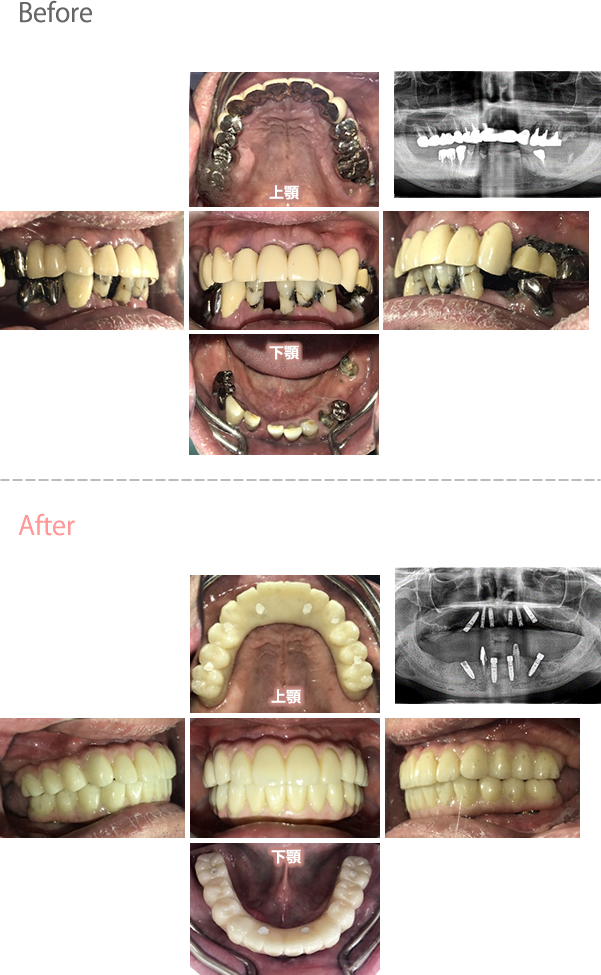

歯がグラグラするところ、むし歯のところ、しみるところ、被せ物がとれたところ、歯茎が腫れて血が出るところ、歯が抜けているところがある。すべて治したい。

残っている歯を抜歯し、上下インプラント治療をしました。

歯周病が進行している歯、むし歯が進行している歯がほとんどで、レントゲンを撮り、詳しく診てみると、ほとんどの歯を保存することができないことがわかりました。抜歯後は、入れ歯かインプラントの方法があります。治療開始前に患者さんに詳しく現状を説明し、治療法についてじっくり相談しました。自分の歯と同じような感覚で食事できるインプラント治療を選択されました。治療後、表情がとても明るくなり、口元がとても自然で10歳以上若返ったように感じました。「時間はかかりましたが、インプラントにして本当に良かったです!」と素晴らしい笑顔でお話ししてくださいました。